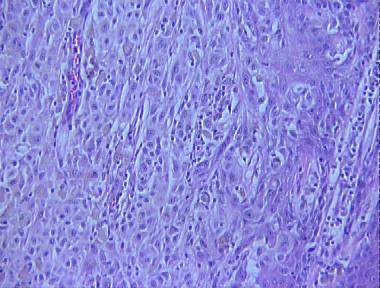

malignant melanoma, nodular type (nodular melanoma)

Histologic Features

- A proliferation of atypical melanocytes as solitary units and nests throughout the entire thickness of the epidermis

- Nest of atypical melanocytes in the dermis of varying sizes and shapes forming sheets of neoplastic cells in the dermis

- Absence of maturation of the melanocytes with descent into the dermis

- Mitotic figures near the base of the lesion